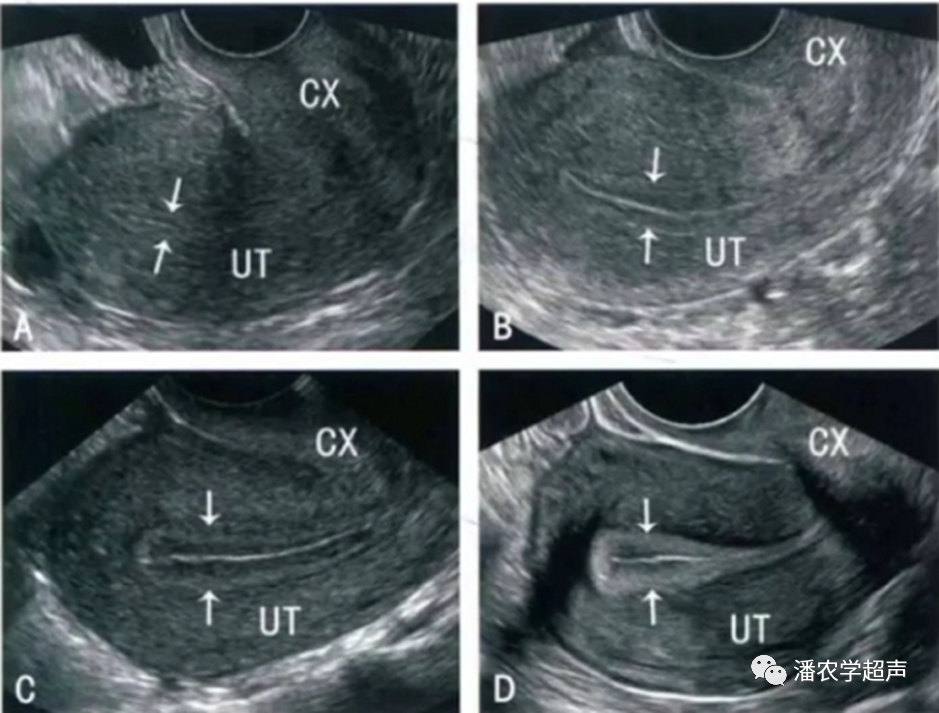

子宫内膜类型

•Gonen标准可以分为3种类型:

A型:典型三线型或多层子宫内膜,两条外层和中央线为强回声线,外层与子宫腔中线之间为低回声或暗区;

B型:宫腔内两条外层线之间为均一的中等强度回声,子宫腔强回声,中线断续不清;

•C型:均质强回声,无子宫中线回声。

内膜形态根据Sher等提出的两级分法判断,即多层(三线型内膜、光晕型)和非多层(均质强回声或与肌层回声不同的均质内膜)。

图A月经期子宫内膜,图B增生期子宫内膜,图C分泌早期子宫内膜,图D分泌晚期子宫内膜(中国妇科超声检查指南)